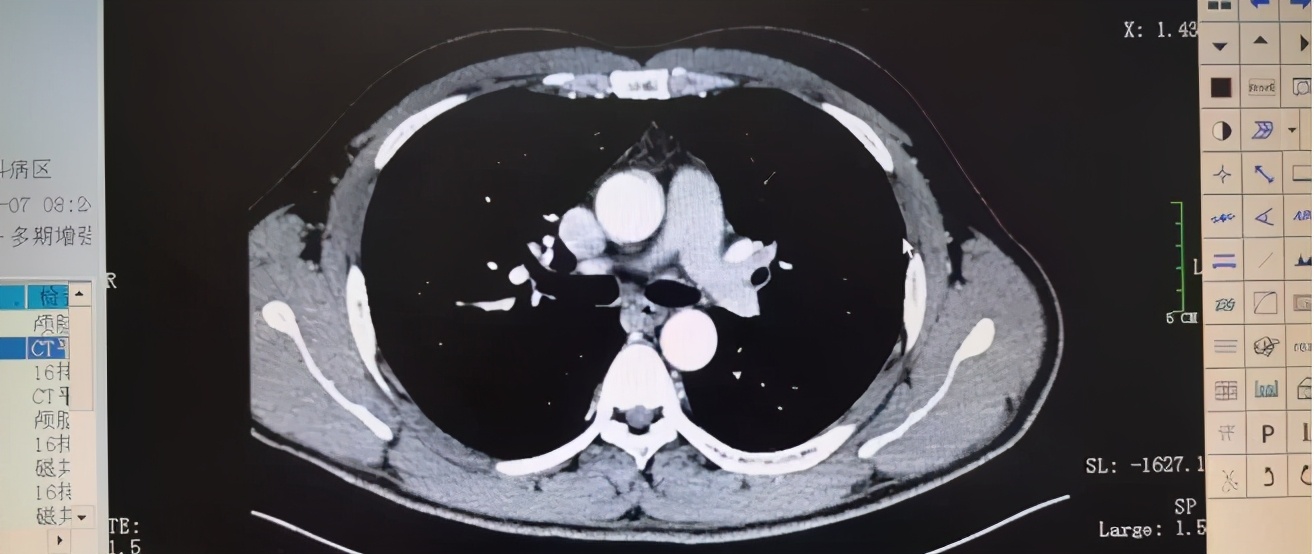

(张伟治疗前的CT显示,图源郑州人民医院)